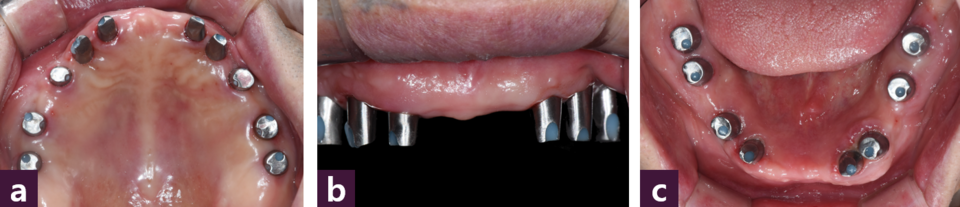

작업 모형을 제작한 후 상하 작업 모형을 반조절성 교합기에 마운팅하여 맞춤형 지 대주(titanium customized abutment)와 상하악 모두 전치부와 양측 구치부로 3분획한 PMMA 임시치아를 제작하였다 [그림 7].

수술 8일 후 구강내에 positioning jig를 이용하여 맞춤형 지대주를 위치시키고 [그림 8]

시멘트유지형 PMMA 임시 치아를 tempbond 임시 시멘트로 접착하였다 [그림 9].

식립 3개월 후 최종 보철물을 제작하기 위해 임시 보철물을 부분적으로 제거한 후 abutment level로 인상을 채득하고 교차 마운팅을 위한 바이트를 채득하여 상악 전치, 하악 전치, 하악 구치, 상악 구치 순으로 zirconia 보철물을 제작하였다 [그림 10].

본 환자는 각각의 임플란트축의 차이가 존재해 맞춤 지대주를 사용하였으므로 passive fit을 얻는데 주안점을 두어 시멘트 유지형 보철물로 수복하였다.

최종 보철물은 보철물의 passive fit, 청소성, 탈착 가능성의 측면을 고려하여 상악은 전치부와 구치부로 3분획하고 하악은 전치부, 우측 구치부, 좌측 소구치부, 좌측 대구치로 4분획하여 제작하였다.